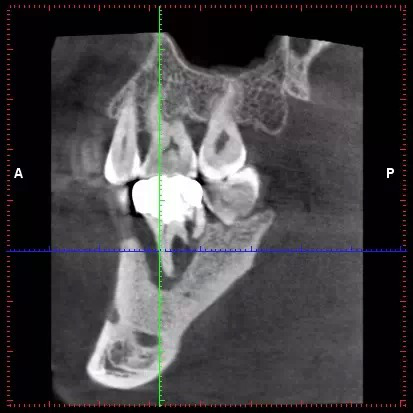

最近的研究有 · 4因素影響即刻種植效果

- 骨增量